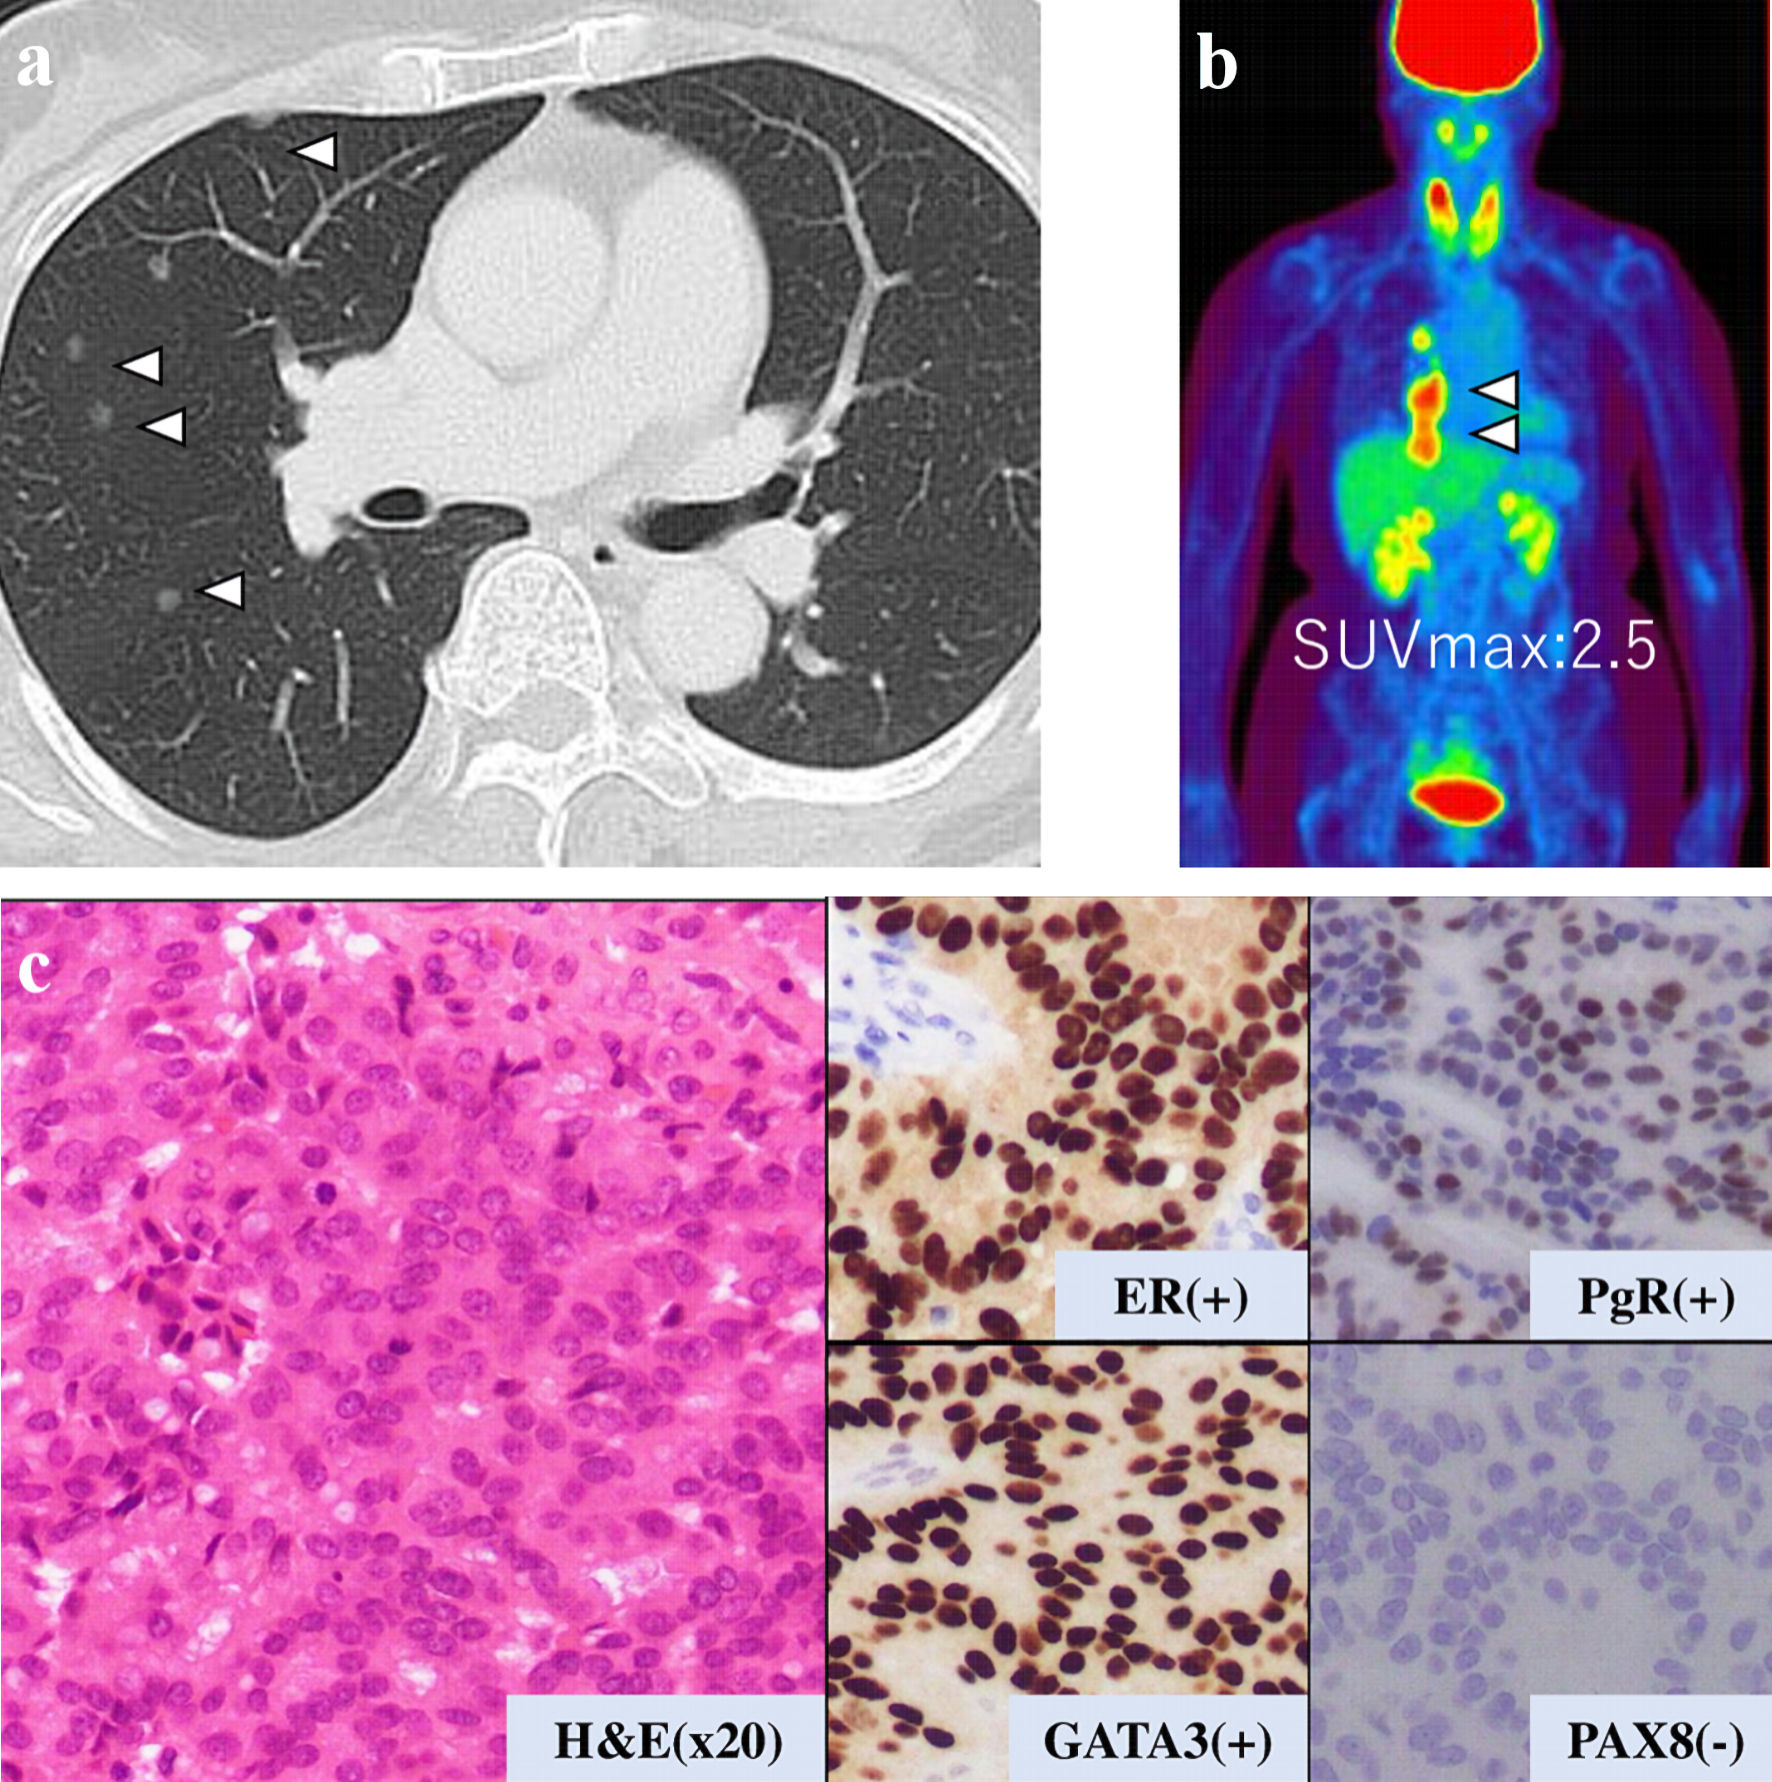

This is a case of a 42-year-old woman with hypothyroidism as comorbidity. The family history revealed that her mother had lung cancer, her paternal aunt had breast cancer, her paternal uncle had pancreatic cancer, and her maternal uncle had prostate cancer and malignant lymphoma. She presented with a left breast mass with pain. A core needle biopsy of breast mass showed invasive ductal carcinoma (IDC). After several examinations, such as computed tomography (CT) and magnetic resonance imaging (MRI), she was diagnosed with 13 × 13 mm breast cancer (cT1N0M0) and underwent breast-conserving surgery with sentinel lymph node biopsy. Pathological analysis showed 12 × 10 mm of IDC with nuclear grade 1, estrogen receptor (ER)-positive, progesterone receptor (PgR)-positive, and human epidermal growth factor receptor 2 (HER2)-negative (pT1N0M0, stage I) (Fig. 1a). She received adjuvant radiotherapy (50 Gy) and endocrine therapy (tamoxifen). At the age of 45 years, the follow-up CT scan revealed a tumor in the uterus (Fig. 2a). She was diagnosed with endometrial cancer and underwent a laparoscopic modified radical hysterectomy with bilateral oophorectomy with pelvic lymph node dissection. Pathological analysis showed localized endometrioid adenocarcinoma, exophytic type, ly0, v0, margin (-), grade 1 (pT1aN0M0) (Fig. 1b). Then she received six cycles of adjuvant chemotherapy, combined with paclitaxel and carboplatin. One year after, the follow-up CT scan revealed multiple intraabdominal masses (Fig. 2b). As peritoneal dissemination from breast or endometrial cancer was suspected, laparoscopic peritoneal dissemination resection was performed. Pathological analysis of peritoneal tumor confirmed the dissemination of endometrioid adenocarcinoma (Fig. 1c). Ten years after breast cancer surgery, mass lesions were noticed in her thoracic cavity on a follow-up CT scan (Fig. 3a). The positron emission tomography-computed tomography (PET-CT) scan showed an accumulation of maximum standardized uptake value (SUVmax) = 2.5 (Fig. 3b). Video-assisted thoracoscopic surgery was performed to identify the primary lesion of this tumor. The pathological analysis revealed the tumor positive for ER, PgR, and GATA binding protein 3 (GATA-3), which led to the diagnosis of metastasis from breast cancer (Fig. 3c).

![]() Click for large image | Figure 3. Examination results for mass in her thoracic cavity by (a) CT, (b) PET-CT (SUVmax = 2.5), and (c) pathological analysis. ER: estrogen receptor; PgR: progesterone receptor; H&E: hematoxylin and eosin stain; CT: computed tomography; PET-CT: positron emission tomography-computed tomography; SUVmax: maximum standardized uptake value. |